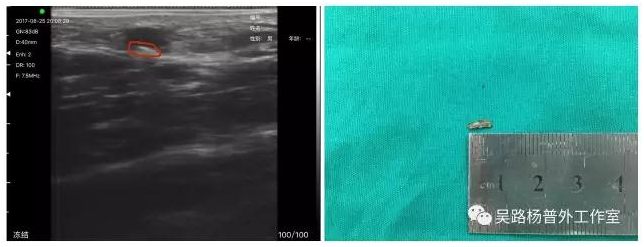

体内异物的术前、术中定位

射入体内异物因为射入的角度和速度不同,距离皮肤的伤口的距离和深度有时很难把握,术中C臂透视只能定位金属异物,非金属就爱莫能助了。无线超声既可以术前定位更可以术中实时引导操作。